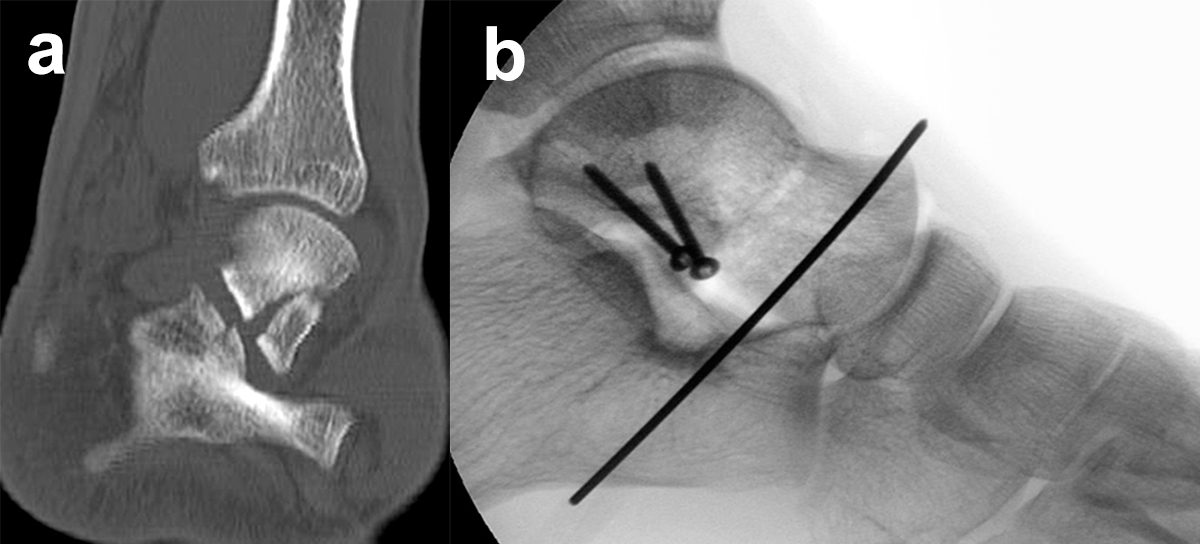

Eine exakte Abgrenzung von Taluskorpus- und Talushalsfrakturen ist allein anhand von Standard-Röntgenaufnahmen nicht sicher möglich. Inokuchi und Mitarbeiter definierten daher Talushalsfrakturen mittels CT, wobei die Frakturlinie distal vor dem Proc. fibularis talis ausläuft 6 (Abb. 1). Es ist anzunehmen, dass sich mit dieser Definition die oben angegebenen Zahlen von den Talushalsfrakturen etwas zu den Taluskorpusfrakturen verschieben, zumal diese mehrheitlich anhand von Röntgenaufnahmen erhoben wurden.

Prinzipiell werden konventionelle Röntgenaufnahmen vom OSG in 2 Ebenen (a.p. in 20° Innenrotation, „Mortise View“, und lateral) angefertigt (Abb. 1a, b). Zusätzlich können spezielle Projektionen wie die Canale oder Brodén-Aufnahme hilfreich sein, wurden in der klinischen Routine aber durch das CT oder DVT weitgehend verdrängt.

Bei in den konventionellen Aufnahmen nicht sicher auszuschließender Talusfraktur bzw. zur genauen Darstellung der Dislokation bei Taluskorpus- oder Talushalsfraktur sollte die Indikation zur CT-Diagnostik großzügig gestellt werden (Abb. 1 c, d). Insbesondere dient die CT-Diagnostik zur genauen Evaluierung der Frakturmorphologie und OP-Planung sowie auch zur Vermeidung möglicher übersehener peripherer Talusfrakturen 4.